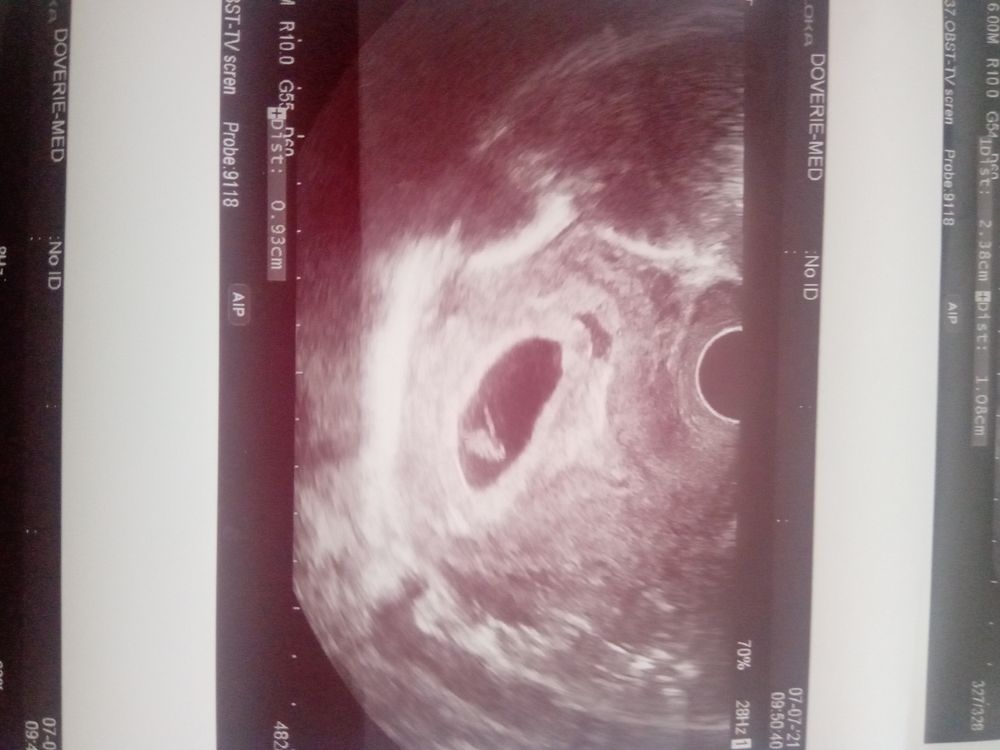

В 7 недель третья и четвертая были ктр 9 мм, ПЯ 25 мм. ЖМ не измеряли почему-то. Изображение